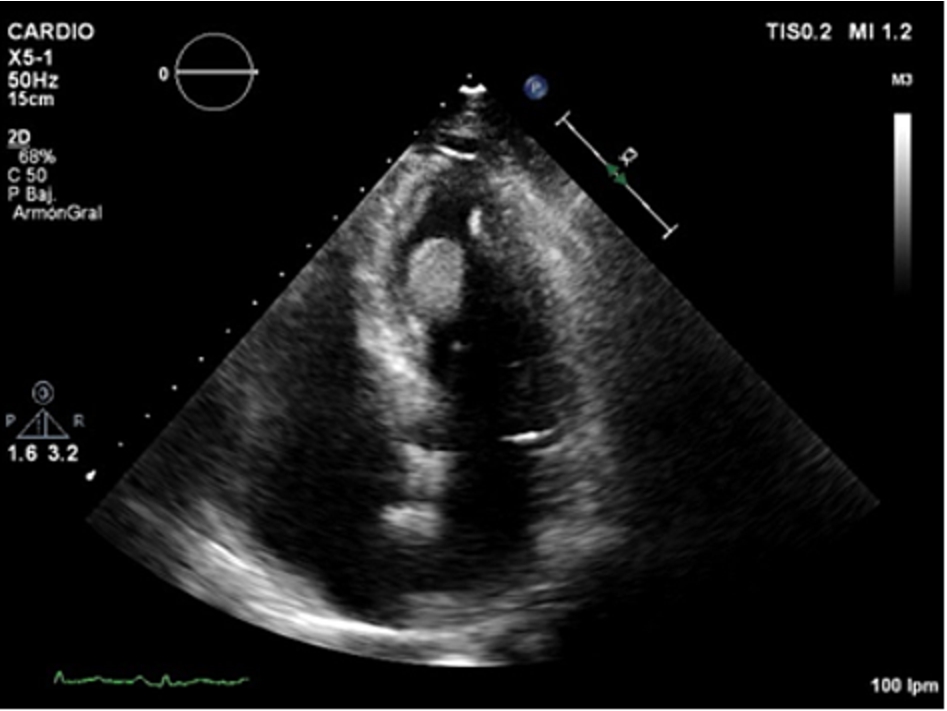

PET-study demostered lung and bone lesions and also mass in the left ventricle. A transthoracic 2D-echocardiogram was performed (Movie I in the Data supplement), showing a mass in the left ventricle.

Figure 1.

Apical four-chamber echocardiographic view. Left ventricular mass attached to inferior interventricular septum.